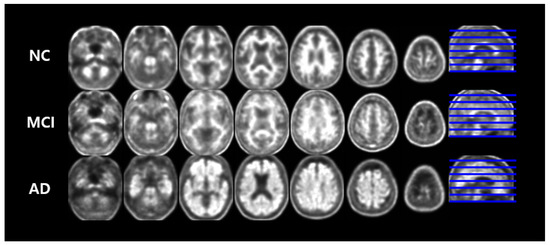

3.2. Dataset